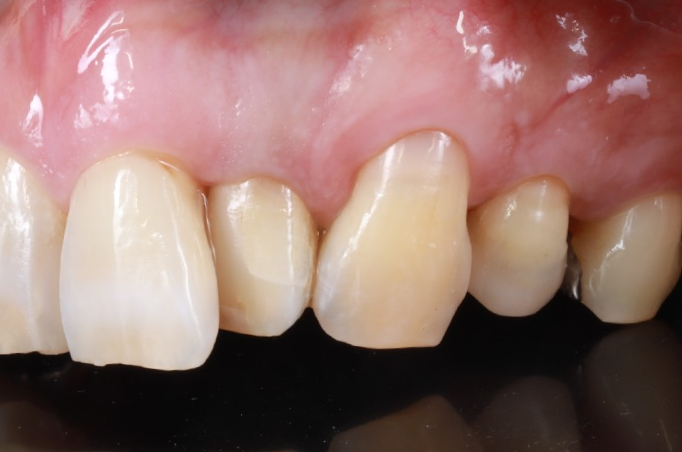

症例5

| 項目 | 詳細 |

|---|---|

| 患者様データ | 40代 男性 |

| 来院時の主訴 | 「歯が黒くなってきたのを治したい。冷たいものでしみる。」 |

| 医院の診断 | 左上側切歯は失活による変色 左上犬歯は非う蝕性歯頸部歯質欠損と歯肉退縮 左上第1小臼歯は銀歯による審美障害とう蝕 |

| 通院期間 | 3か月 |

| 来院回数 | 6回 |

| 治療費 | 総額:105,000円(税抜) 【内訳】 前歯ホワイトニング10,000円、歯頸部ダイレクトボンディング10,000円、セラミック治療85,000円・リスクと副作用:定期的なメインテナンスが必要・長期的には着色してくる可能性あり |

| リスクと副作用 | 定期的なメンテナンスが必要、術後若干の腫れと痛み |

| ここがこだわりのポイント!☝ | 歯肉退縮すると根面う蝕になりやすくなります。歯頸部のえぐれた歯肉退縮部位にCR充填し 歯磨きをしやすくすることで、根面う蝕の予防を目指しました。 |